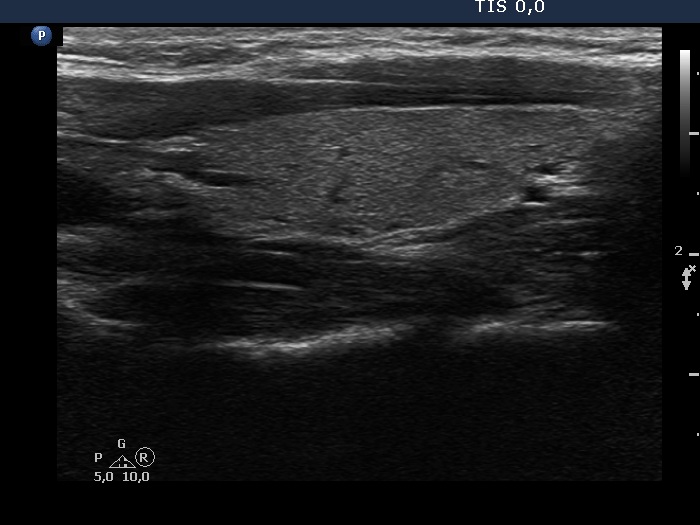

100 consecutive cases of papillary cancer - case 087 (ultrasonographic picture 6)

Left lobe, longitudinal scan.